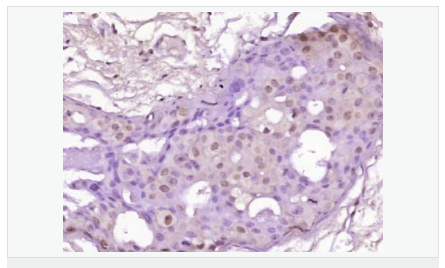

| 產品應用 | WB=1:500-2000 ELISA=1:5000-10000 IHC-P=1:100-500 IHC-F=1:100-500 Flow-Cyt=0.2μg /test IF=1:100-500 (石蠟切片需做抗原修復) not yet tested in other applications. optimal dilutions/concentrations should be determined by the end user. |